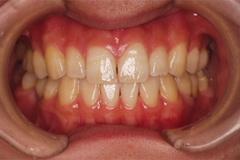

口内写真とパノラマレントゲンを撮影し、まずは顎の骨の状態まで詳しく確認しました。

写真(1)口内写真

歯がない期間が長く続いたため隣の歯が横に倒れてしまい、歯と歯との間に隙間が2ケ所できてしまっていたため、インプラントの前に矯正治療で隙間をなくす治療を行う